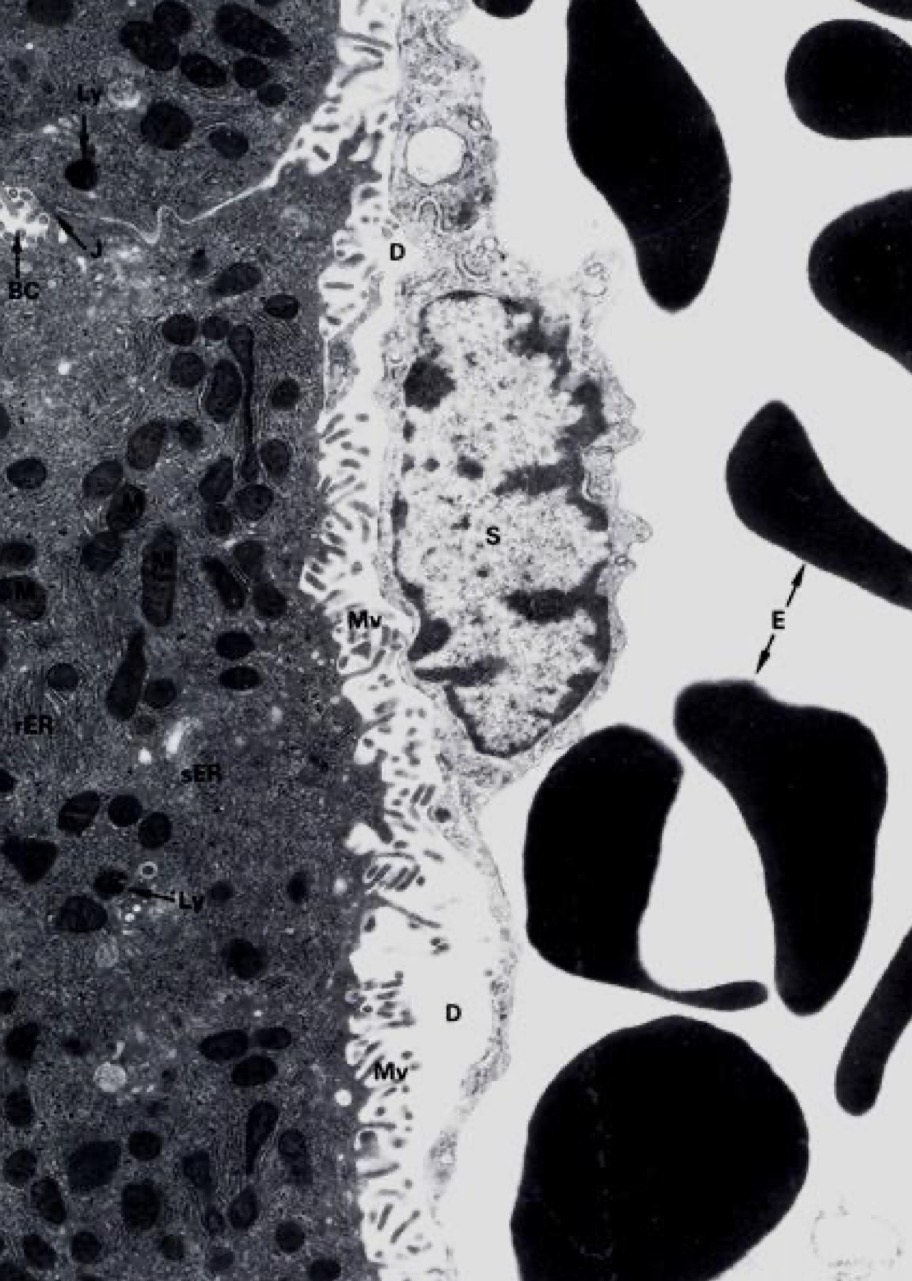

Identify the Organ and Structures?

Liver;

1 = Space of Disse

2 = Sinusoid

3 = Endothelium (simple squam)

4 = Hepatocyte

Function of Space of Disse?

intimate contact w/ hepatocyte MV and sinusoid, support is reticular f/Stroma

Liver; MV of hepato next to dark on the L, D = space of Disse, L of cow print is endothelium of suni